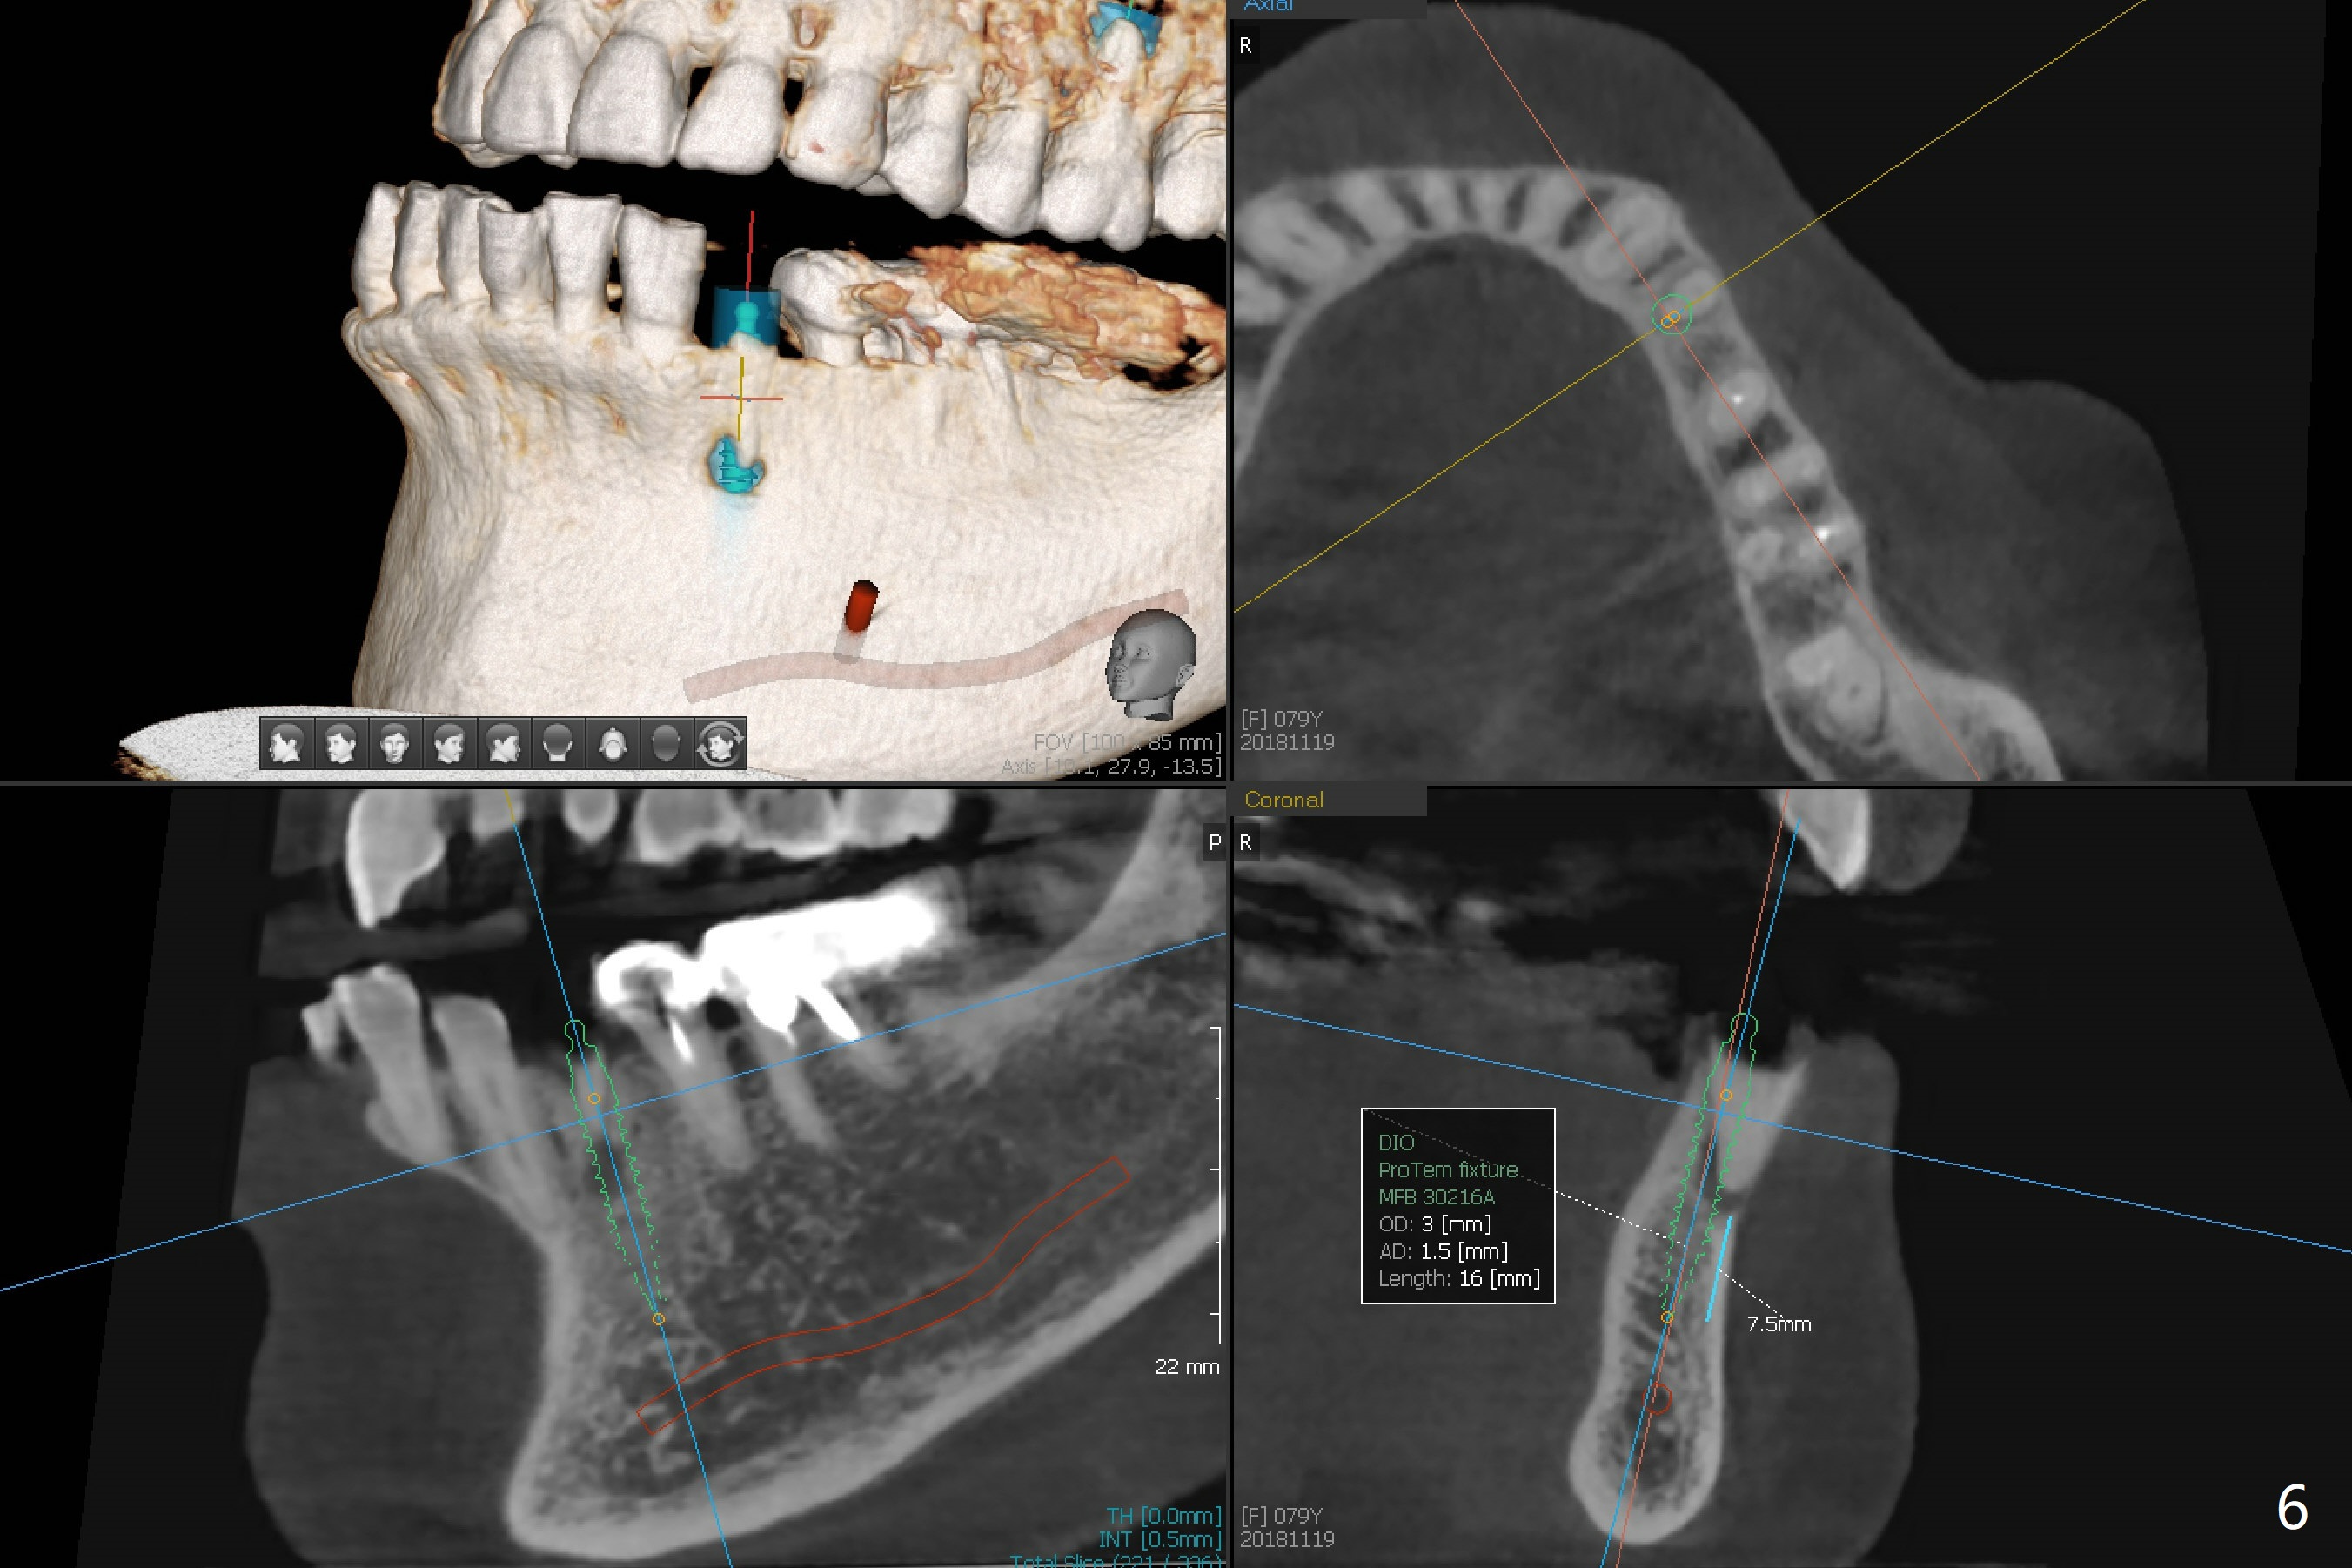

A 79-year-old woman has subgingival symptomatic caries at #14 and residual roots at #4 and 21 (Fig.1). Because of bilateral thick sinus membrane (Fig.2 *) with nasal obstruction, immediate implants at #14 and 4 will be placed without sinus lift (Fig.3,4). To obtain primary stability, a long implant will be placed at #21 (15 or 16 mm), while a narrower implant (3 mm 1-piece, Fig.6)) is safer than 3.8 mm one (2-piece, Fig.5) in term of preventing periimplantitis (buccal thread exposure). Impression has been taken for guide at #14.